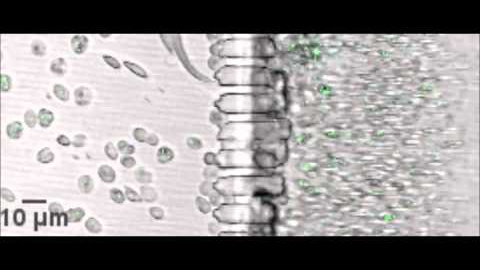

Los investigadores han logrado elaborar un modelo funcional de bazo en 3D que actúa como éste órgano filtrando los glóbulos rojos de la sangre. Lo que se ha logrado es recrear a microescala las propiedades físicas y las fuerzas hidrodinámicas de la unidad funcional de la pulpa roja del bazo.

La unión de ambos equipos ha dado lugar a un avance pionero en todo el mundo, explica: "Ya ha habido avances en este sentido, pero al contrario de lo que se había logrado hasta ahora, que eran dispositivos de filtrado, lo que hemos conseguido es emular exactamente lo que pasa en nuestro órgano cuando pasa la sangre y lo que sucede cuando pasan los glóbulos rojos viejos o los parasitados".

El bazo en un chip ya ha sido probado con sangre humana y sangre parasitada por la malaria y todo está funcionando correctamente. Ahora los responsables del estudio piensan ya en los próximos pasos.